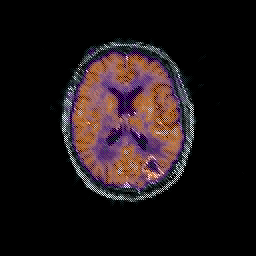

Glioma overlay -- Slice #67

[Home][Help][Clinical] Slice 67